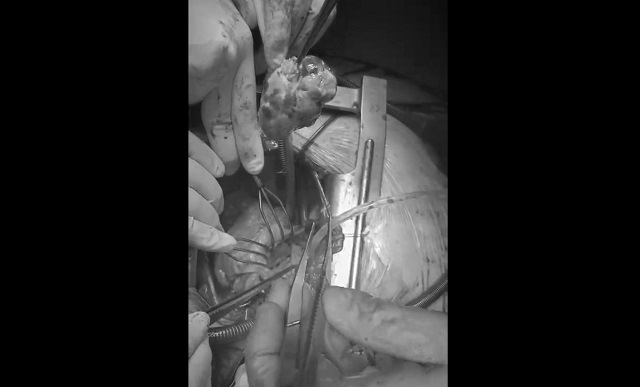

Новообразование заняло практически весь жизненно-важный орган изнутри.

Гигантскую опухоль из сердца 71-летней пациентки через небольшое отверстие удалили врачи Больницы скорой медицинской помощи Набережных Челнов, передает пресс-служба медучреждения.

Медики рассказали, что новообразование заняло практически весь жизненно-важный орган изнутри. Кроме того опухоль практически продавила важнейший митральный клапан.

«Наши доктора не только успешно удалили опухоль, но и заменили «испорченный» митральный клапан сердца. Теперь нашей пациентке ничего не угрожает», — сообщили в БСМП.